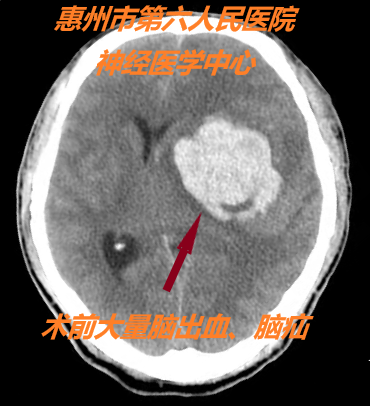

患者到達六院,預(yù)先接到電話的急診醫(yī)學(xué)科迅速接診,確認(rèn)一側(cè)瞳孔散大,立即為患者暢通急救通道,優(yōu)先送放射科急查CT,結(jié)果提示:左側(cè)基底節(jié)腦出血并腦疝形成。神經(jīng)外科醫(yī)生也第一時間趕到急診醫(yī)學(xué)科會診聯(lián)合搶救,啟動腦疝急診手術(shù)綠色通道流程進行搶救,爭分奪秒挽救生命。

病情就是命令。一旦發(fā)生腦疝,就意味著時間就是生命,晚幾分鐘都有可能導(dǎo)致嚴(yán)重殘疾或長期植物狀態(tài)甚至死亡。神經(jīng)外科醫(yī)療團隊立即與手術(shù)室、麻醉科取得聯(lián)系,開通急診手術(shù)綠色通道,直接將病人送入手術(shù)室,給患者創(chuàng)造一個最佳的“黃金搶救時段”,用最短的時間做好術(shù)前準(zhǔn)備。神經(jīng)外科主任余永強、麻醉科主任蔡劍波帶領(lǐng)神經(jīng)外科及手術(shù)室團隊立即進行插管全麻開顱顯微手術(shù)搶救,清除腦內(nèi)血腫。術(shù)后CT顯示血腫全部清除,患者生命體征平穩(wěn),轉(zhuǎn)入神經(jīng)外科重癥監(jiān)護室繼續(xù)治療。